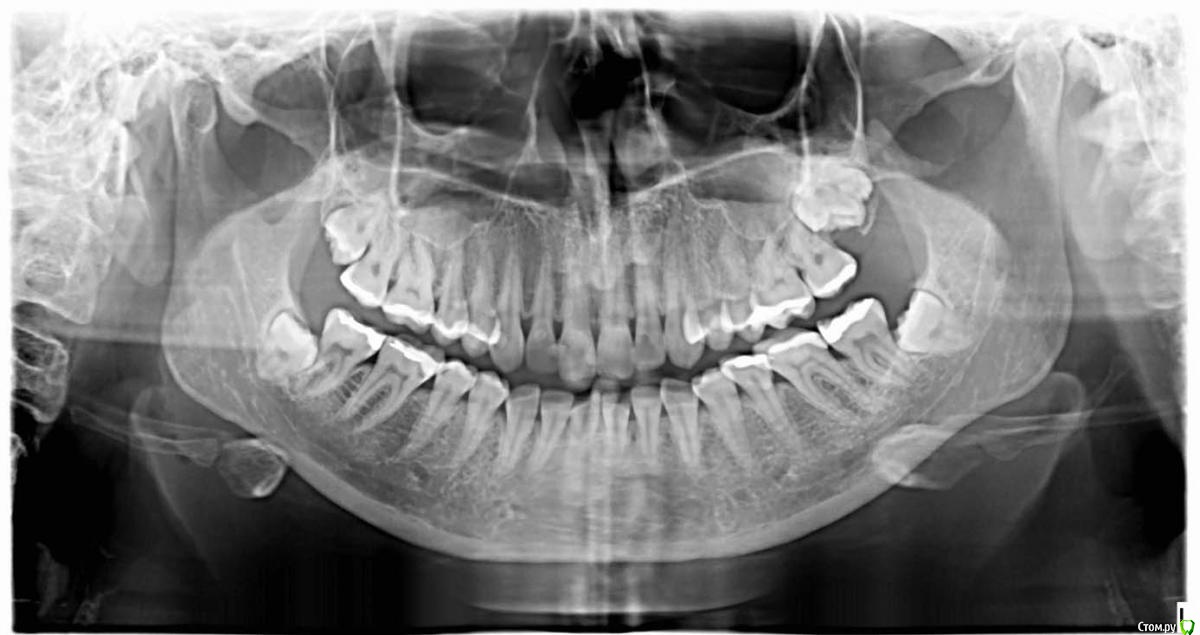

sonoko Опубликовано 21 мая, 2015 Поделиться Опубликовано 21 мая, 2015 (изменено) Добрый день! Собираюсь удалять все свои 4 восьмёрки и хотела бы получить тут консультацию, прежде чем идти к хирургу. Год назад прорезалась верхняя правая восьмёрка (маленький кусочек зуба торчит из нижней поверхности десны), и лечащий врач посоветовал её удалить. Остальные восьмёрки не прорезались. Болезненных ощущений от зубов мудрости не испытываю (иногда несильно "тянет" в области левой нижней восьмёрки), но чувствую, что правая верхняя стала немного подпирать щёку сквозь десну. Пожалуйста, подскажите, сложен ли мой случай? (Да, возможно, я чуть-чуть паникую , но моя ортопантограмма меня неприятно удивила.)Какая из восьмёрок подлежит удалению в первую очередь, и стоит ли оставлять левую верхнюю - вроде как ей есть куда расти? Насколько я могу понять, правая верхняя растёт вбок, но при удалении это ведь не должно вызвать особых проблем? Больше всего меня беспокоит ситуация с левой нижней. Если я правильно интерпретирую снимок, она полностью закрыта: с трёх сторон костью, с четвёртой - соседним зубом. Я бы не стала её трогать, но меня тревожит наличие тянущих и распирающих ощущений, возникающих время от времени. Боюсь, что её рост повредит соседний зуб. Насколько сложным является удаление такого зуба? Можно ли делать его в поликлинике, или лучше обратится в больницу, в отделение челюстно-лицевой хирургии? Заранее спасибо за ответы. Изменено 21 мая, 2015 пользователем sonoko Ссылка на комментарий

diesel87 Опубликовано 21 мая, 2015 Поделиться Опубликовано 21 мая, 2015 Удаления не сложные, для не прорезавшихся восьмерок, слева кстати сверху возможно еще девятка есть. Если каждый визит к стоматологу сложен и страшен, то можно под седацией все 4 сразу или же по две с каждой стороны для удобства адаптации. 1 Ссылка на комментарий

sonoko Опубликовано 22 мая, 2015 Автор Поделиться Опубликовано 22 мая, 2015 (изменено) Большое спасибо всем за ответы! Радует, что случай мой вполне заурядный (ну, за исключением девятки - из-за неё я и решила, что снимок отзеркален: приняла левые 8+9 за мою единственную почти "проклюнувшуюся" правую восьмёрку.) Я и не подозревала, что девятки вообще существуют. Страха перед визитами к стоматологу у меня нет: к сожалению, зубы плохие, и редкие полгода-год обходятся без новой пломбы. Но все мои посещения зубного в этом году были с нехорошими последствиями: то укол пришёлся в нерв, и левая половина языка онемела почти на месяц, то после отхода от обезболивания все зубы слева стало очень болезненно "дёргать"... А удаление ретинированных зубов всё-таки гораздо более травмирующая процедура, чем установка пломбы. Поэтому перед тем, как идти к хирургу, я хотела знать, к чему мне быть готовой. Всегда сильнее пугает не боль, а недостаток информации. После прочтения ответов появился вопрос: если удалять все за один раз, то не затруднит ли это процесс заживления, ведь во время приёма пищи ранки будут неизбежно травмироваться? Изменено 22 мая, 2015 пользователем sonoko Ссылка на комментарий

diesel87 Опубликовано 23 мая, 2015 Поделиться Опубликовано 23 мая, 2015 Эти восьмерки вам точно не пригодятся, учитывая что они могут подпортить семерки раньше чем появятся на свет. При седации меньше уколов требуется, травмы меньше. 1 Ссылка на комментарий